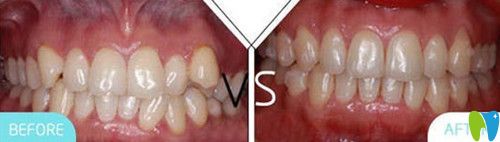

二、牙齒矯正案例:

術(shù)前牙齒癥狀:牙列不齊

術(shù)后牙齒效果:歪斜的牙齒立正了

凱樂口腔牙齒矯正前后對比圖